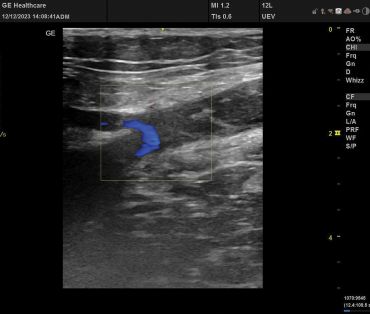

Obr. 2 Lumen VSM na levé dolní končetině před plánovaným zákrokemPři druhé návštěvě nám sdělila, že operaci na varikozitách nepodstoupila, defekty byly ošetřovány cestou dermatologického pracoviště péče o chronické rány. U pacientky byla nastavena i celková ATB terapie. Kompresní terapie neselhávala a v průběhu pěti let došlo k uzavření defektů na PDK a k parciální redukci defektu na LDK. V rámci našeho druhého vyšetření byla diagnostikována progrese insuficientních kmenových žil. Lumen VSM dosahovalo průměru více než 2 cm (obr. 2).